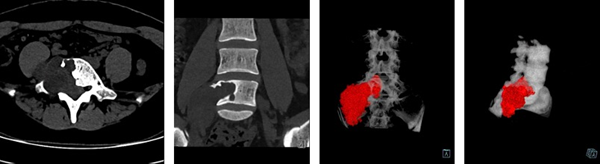

患者为一名25岁的年轻女性,6月前患者无明显诱因出现腰背部及双下肢疼痛,劳累后加重,休息时可缓解,行膏药贴敷外用后症状无缓解。1月前于外院行“腰椎CT”示“腰5椎体改变,多考虑骨巨细胞瘤,为求进一步诊治遂来我院就诊,在骨一科樊立宏主任医师仔细问诊、阅片后,高度怀疑患者椎体破坏并非骨巨细胞瘤,考虑是巨大神经鞘瘤。入院后复查腰椎CT提示“腰5椎体右侧、椎管及椎旁见不规则团片状软组织密度影,较大截面病变大小约65mm×39mm,团块部分伸入椎管”。通过病人病史、查体、肌电图、穿刺病理活检等一系列辅助检查,最终确诊为神经鞘瘤,考虑为巨大神经鞘瘤导致的腰5椎体骨质破坏伴神经受压。腰5巨大神经鞘瘤位于重要血管、神经密布的下腰椎,肿瘤向前突入骨盆、向后突入椎管。术中彻底切除肿瘤、恢复腰椎稳定性并且避免损伤重要血管神经难度大、风险高。

腰椎CT显示腰5椎体严重破坏、软组织突入椎管,考虑为神经源性肿瘤

术前3D打印显示肿瘤与重要血管神经关系紧密,完整切除难度极大